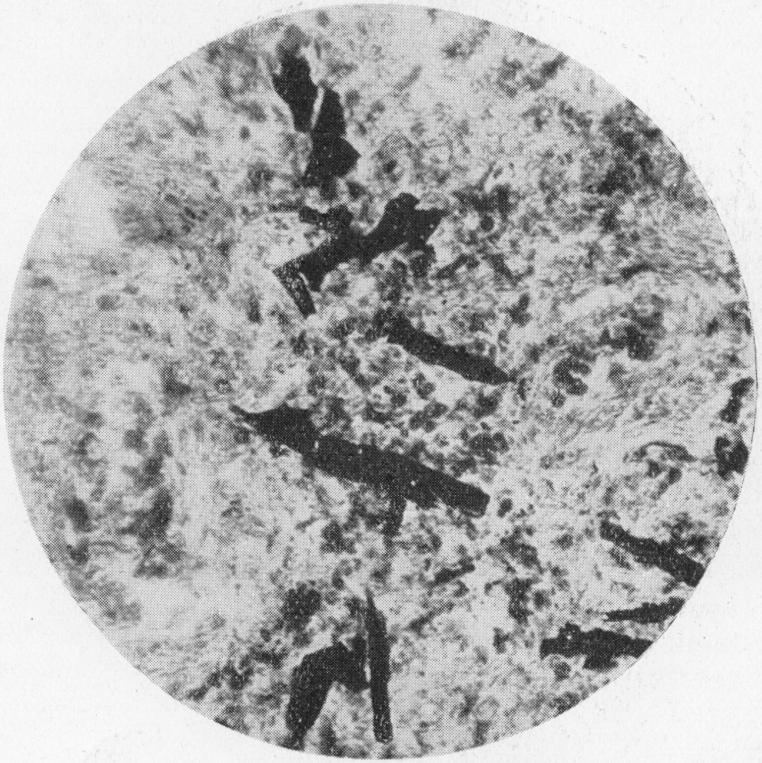

Pulmonary Asbestosis.

Br Med J. 1927 Dec 3;2(3491):1024-5. doi: 10.1136/bmj.2.3491.1024.